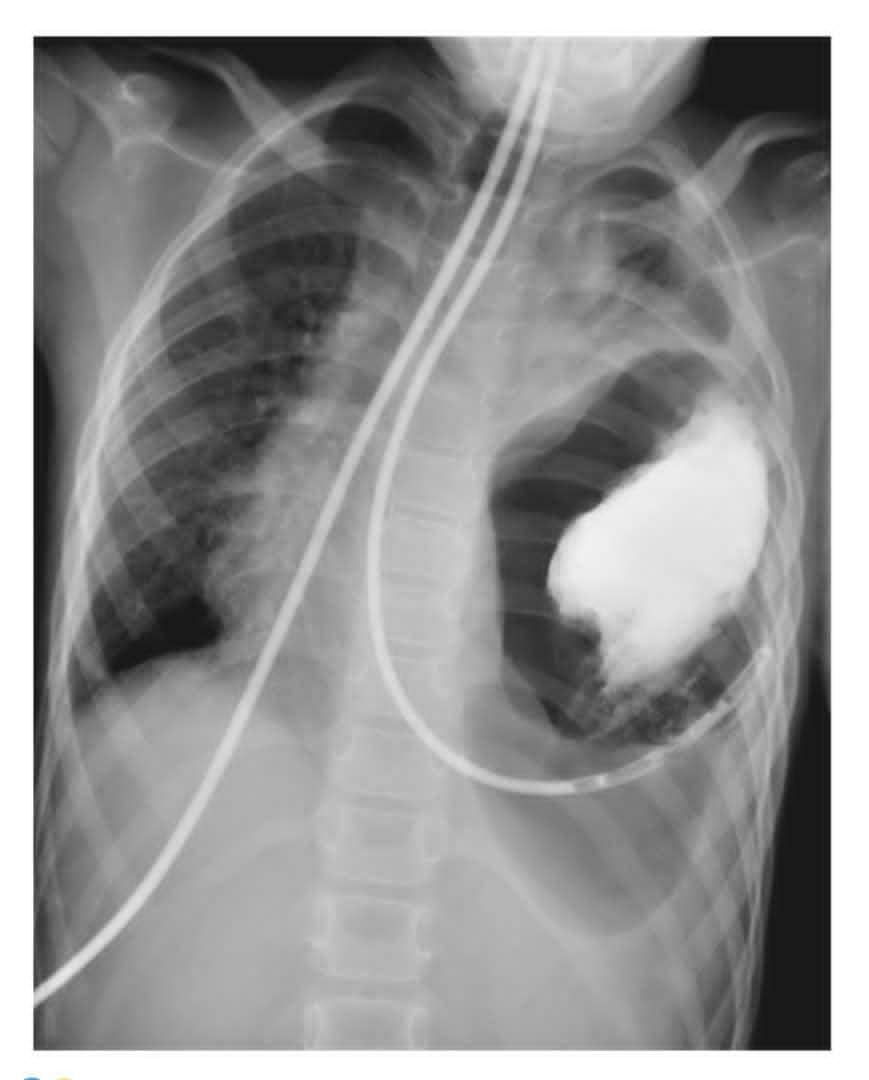

What's your diagnosis?

Dextrocardia ??